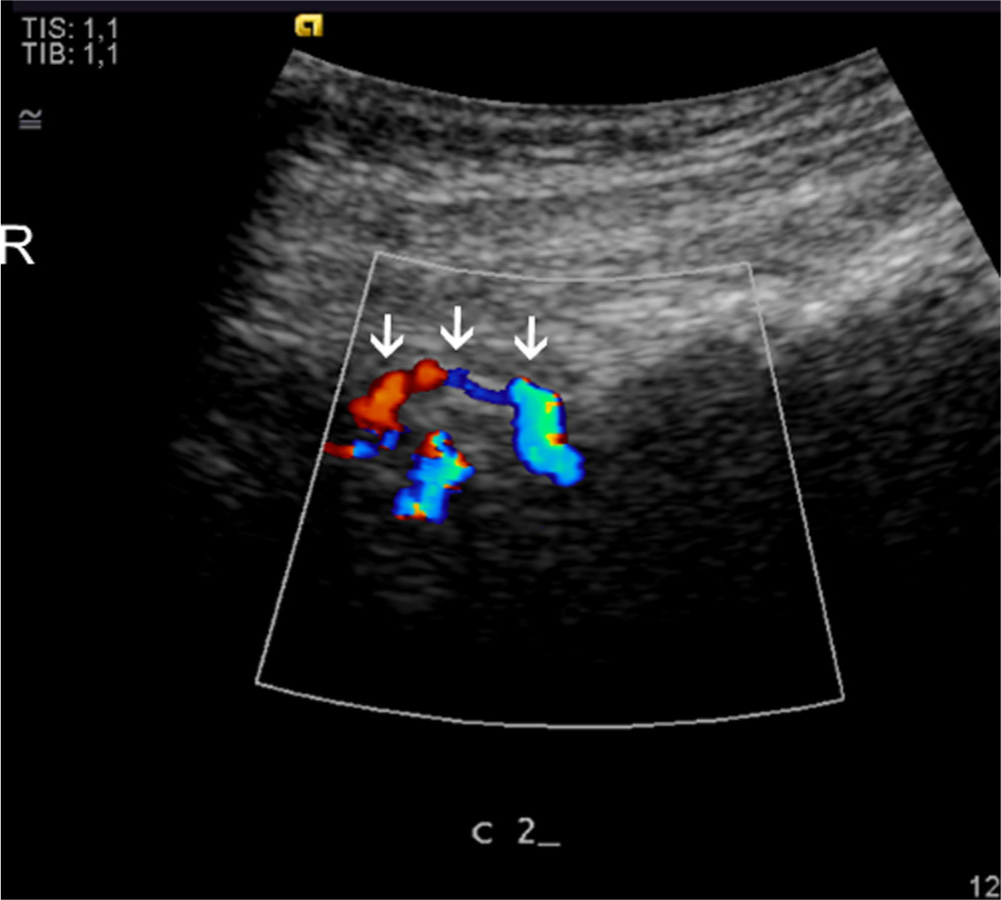

It was not possible to visualize the origin of the blood vessels exactly; however, in the suboccipital region, the high blood flow corresponded to the insertion of the semispinalis capitis and the rectus capitis posterior minor muscles. At the C1 level the high blood flow was more pronounced at the posterior tubercle, corresponding to the insertion of the rectus capitis posterior minor muscles (Figs. 1, Fig. 2, Fig. 3, 4). At the C2 level the high blood flow was found in the region of the spinous process, corresponding to the origin of the rectus capitis posterior major and the obliquus capitis inferior muscles, and bilaterally juxtapositioned to the facet joints (Figs. 5, Fig. 6, 7).

Longitudinal colour, Dopplerscan of a patient. Arrows identify the C2 spinous processes with blood vessels in the tendons. R, rostral.